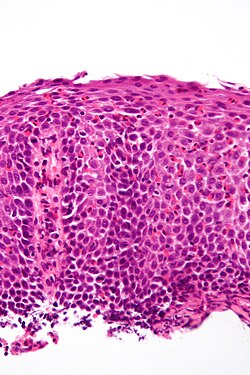

Squamous dysplasia of the esophagus

- AKA esophageal squamous dysplasia.

General

- Precursor of esophageal squamous cell carcinoma.[8]

- Common in China.[8]

- Not very common in North America.

Microscopic

Features:

- Squamous cell nuclear atypia.

- Lack of maturation to the surface.

Note:

- Grading differences between Western pathologists and those of the east.[8]

DDx:

- Reactive changes.

- Esophageal squamous cell carcinoma.